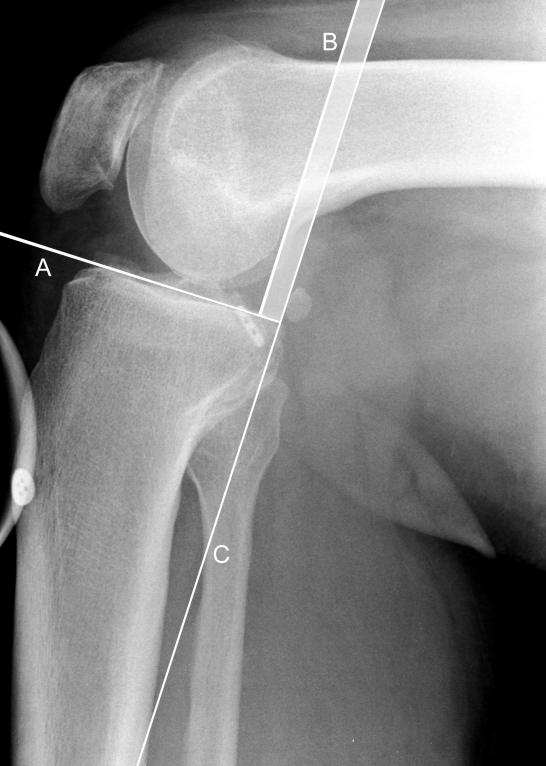

Radiographic imaging studies included CT scans and anteroposterior as well as posterior stress radiographs of both knees (Figure 1 [Fig. 1]). Anatomic healing of the bony avulsions and posterior tibial translation were evaluated by an advanced musculoskeletal radiologist using a PACS workstation (Centricity RIS-I 4.2 Plus, GE Healthcare, Milwaukee, WI, USA). Posterior tibial translation was measured by the use of the Telos device at 90° of flexion with a posteriorly directed force of 150 N at the level of the tibial tubercle. Posterior tibial displacement was measured according to Jacobsen [12] as well as Staubli and Jakob [13] (Figure 2 [Fig. 2]).

Figure 2: Measurement of the posterior tibial translation, using Telos stress device; as described by [12], [13]. Perpendicular to the tangent of the tibial plateau (A), the midpoints between the most posterior contours of the medial and lateral femoral condyles (B) and tibial plateaus (C) are established. The distance between these two points is regarded as the posterior tibial translation and is subsequently assessed in relation to that of the uninjured contralateral knee.